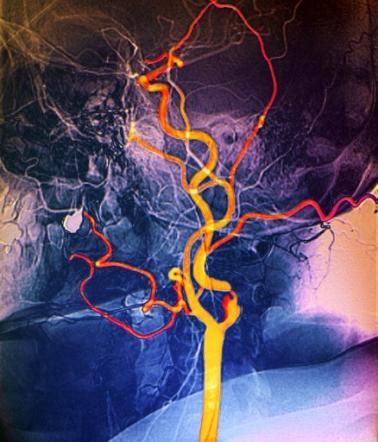

Scoperto un gene anti-ictus, evita i danni ai vasi che ossigenano il cervello